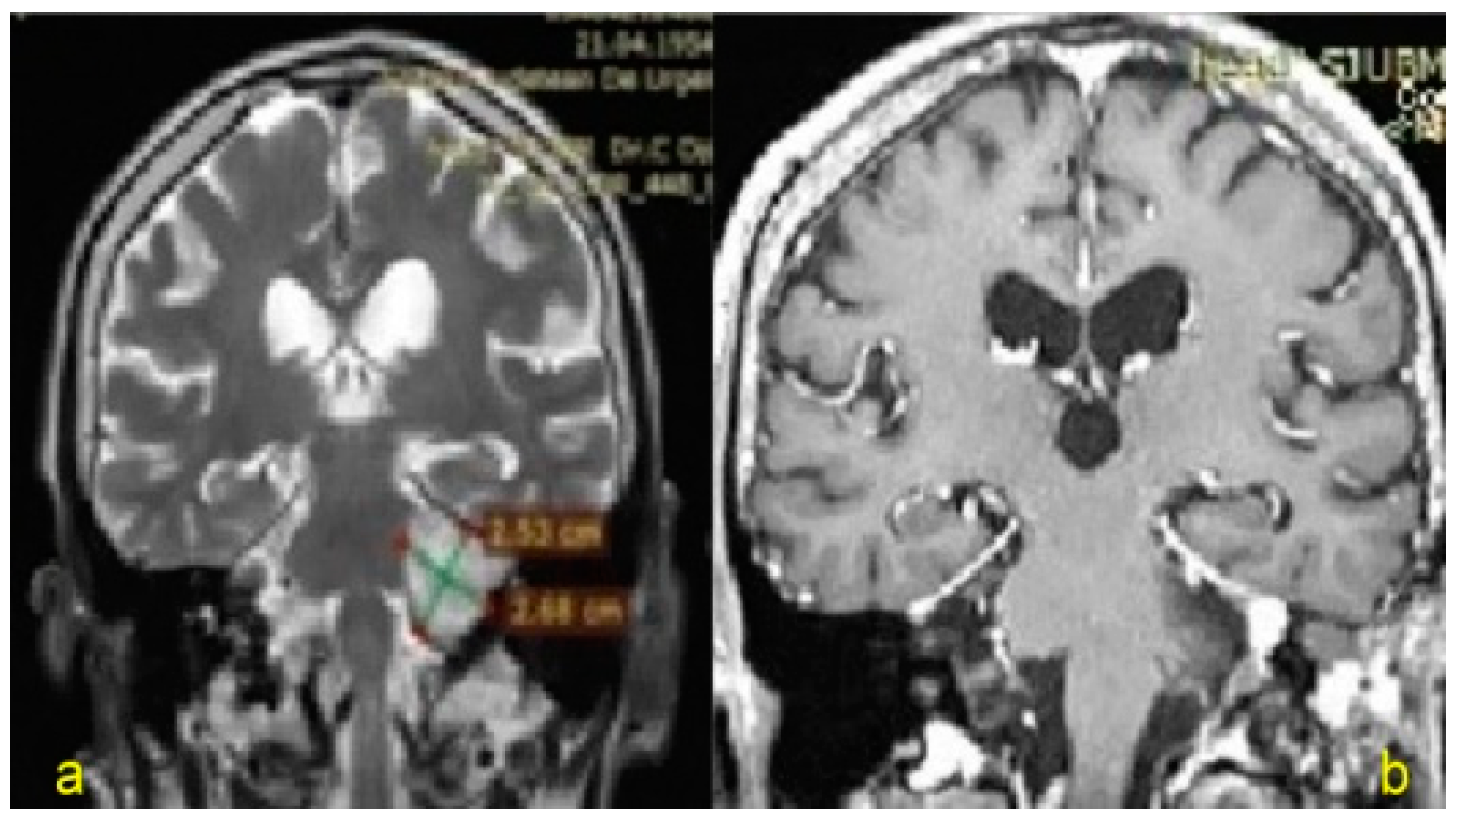

| 3. | 64/M | VS (Apr 2015) Koos grade IV | - | 26 | Tarsorrhaphy | VI/IV (left side) Total paralysis/Disfiguring weakness, incomplete eye closure and asymmetric at rest | CSF leak Hydrocephalus (VCS, right VP shunt) |

| 4. | 63/F | VS (Jan 2018) Koos grade IV | Chronic hypothyroidism (2006) PN—TNSc grade 2 | 6 | Tarsorrhaphy | VI/IV (left side) | - |